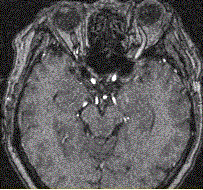

问题 女性,62岁。外伤后左侧突眼。MRI显示如下图。 关于该病,描述正确的是

选项 A.左侧眼上静脉增粗 B.左侧海绵窦增宽 C.左侧颈内动脉增粗 D.颈内动脉变细 E.左侧眼球突出 F.右侧颈内动脉增粗

答案 ABCE